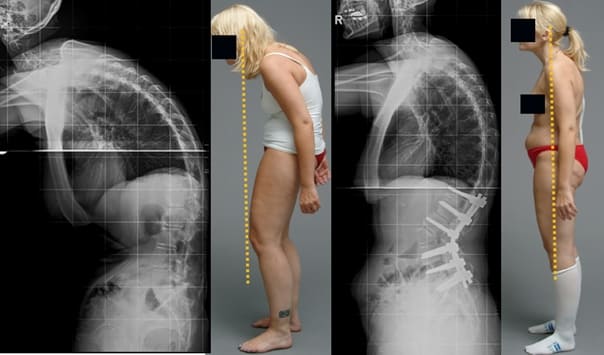

Graças ao Hondrodox, mais de 17 000 pessoas em Portugal evitaram a invalidez e recuperaram a liberdade de movimentos. Aqui estão alguns dos pacientes do professor Afonso Oliveira:

Mulher, 62 anos. Luxação grave da vértebra. O «Hondrodox» restaurou completamente a coluna vertebral em 2 ciclos de tratamento.

Mulher, 42 anos. Deformação grave da articulação do joelho, curvatura dos joelhos. Foram necessários 2 ciclos de tratamento com «Hondrodox» para a recuperação completa.

Homem, 37 anos. Correção completa da postura com Hondrodox em apenas 1 ciclo de tratamento.

Mulher, 51 anos. «Corcunda de viúva» e deformação da coluna vertebral. Eliminação completa da corcunda após 1 ciclo de tratamento com Hondrodox.